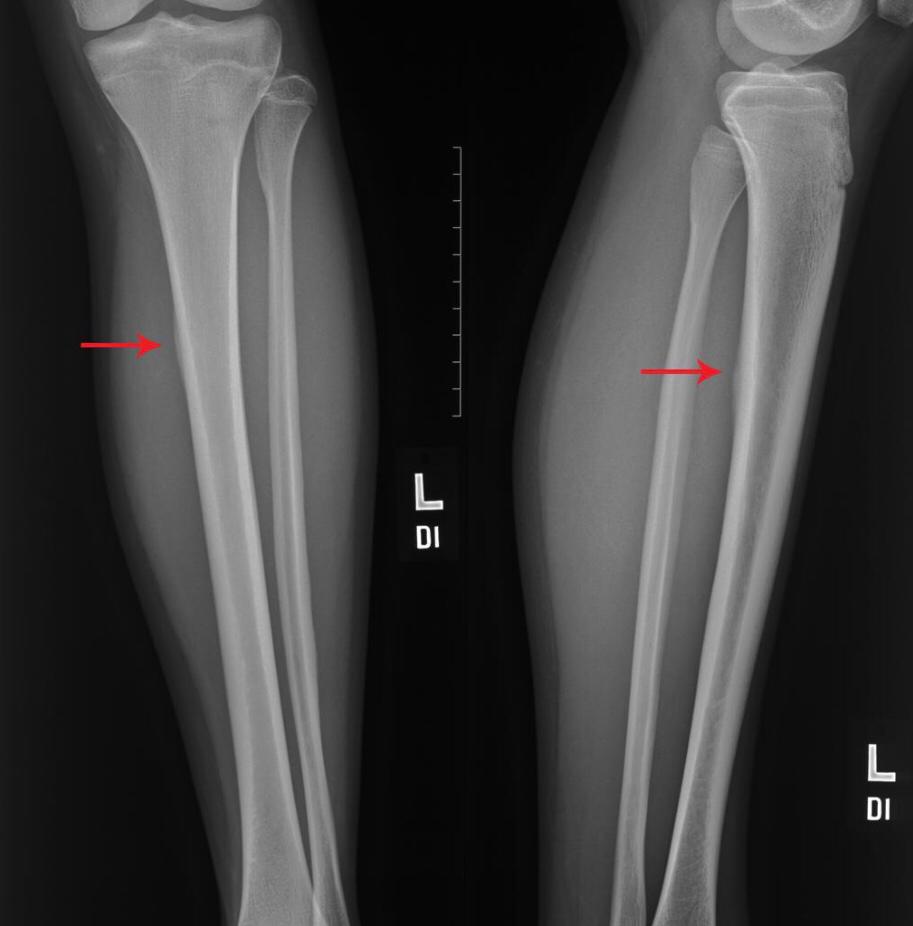

Medial tibial stress syndrome (MTSS), also known as shin splints, describes a spectrum of stress injury that occurs at the medial tibia. This term is often used to indicate any type of tibial stress injury or the earlier manifestations of a tibial stress lesion before a fracture component can be identified. It is considered a low risk stress fracture.

Shin splints are a common exercise-related problem. Typically occurs in athletes (e.g. runners/jumpers) and is characterized by localized pain that occurs during exercise at the medial surface of the distal two-thirds of the tibial shaft, where muscles attach to the bone. Shin splints often occur after sudden changes in physical activity. These can be changes in frequency, duration and intensity.

MRI is the most sensitive radiological examination (~88%). It may demonstrate a spectrum of findings ranging from normal to periosteal fluid to marrow edema to actual stress fracture. The medial cortex (+/- posterior cortex) is most commonly affected.